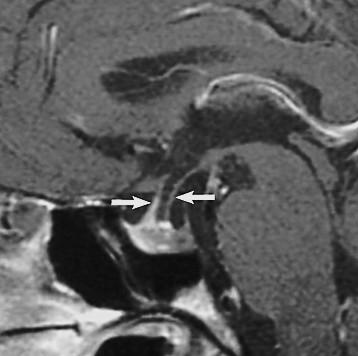

Ectopic posterior pituitary “bright spot.” Missing infundibular stalk.

Contrast or ultra thin T2 needed to confirm.

Thin or truncated stalk

IGHD – Growth Harmone Deficiency if stalk is present but abnormal

PanHypoPit Deficiencies if stalk is completely absent.

Need repeated endocrine evaluations if normal at first imaging.

Neonate: Hypoglycemia, jaundice, Failure to Thrive

Normal or shallow sella

Abscent or hypoplastic stalk Ectopic posterior pituitary